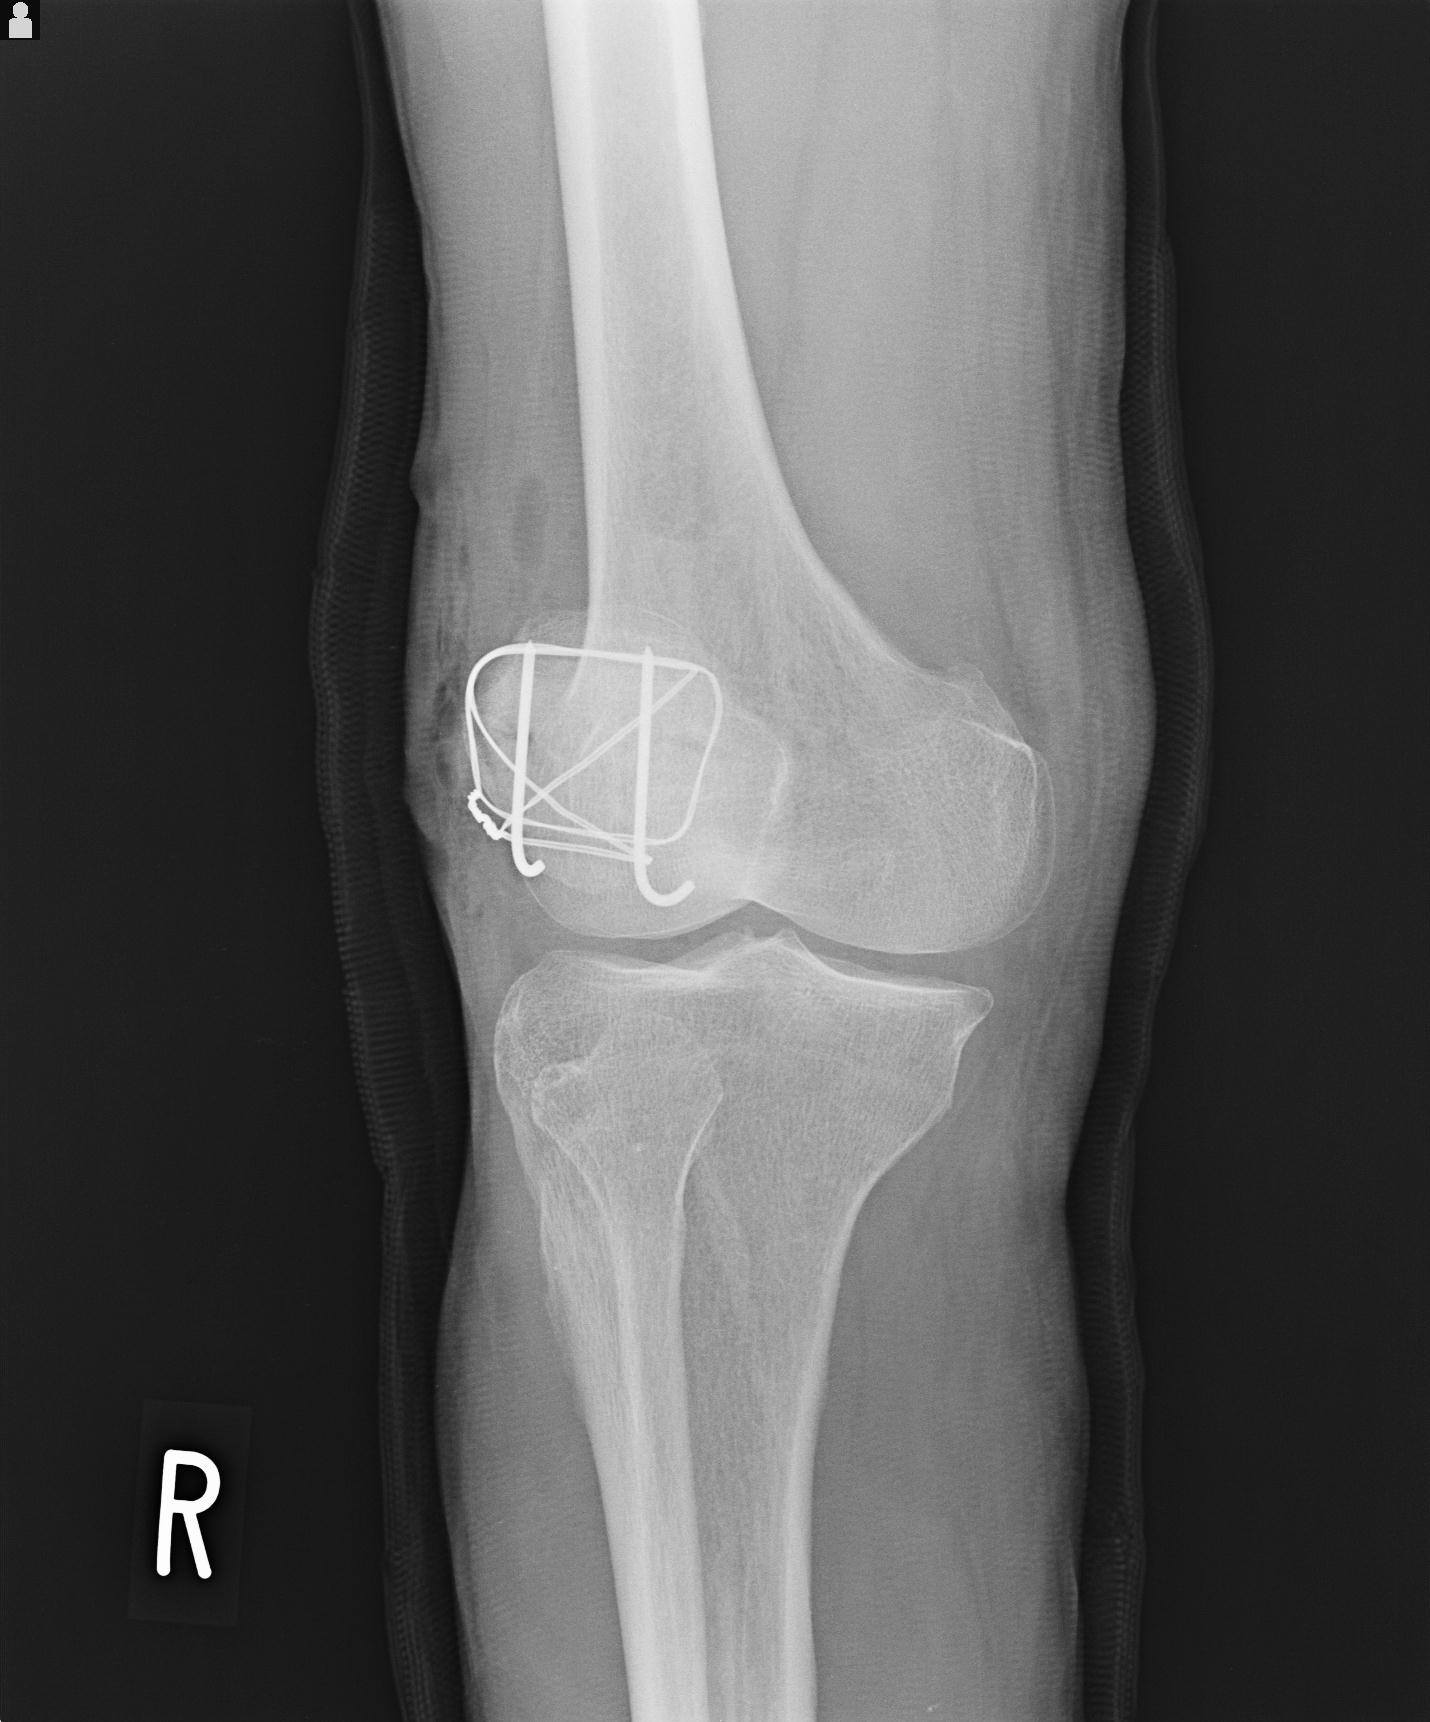

49554 3/13 膝 4R 3/16 4R 1/18 2R 78歳男性 膝蓋骨骨折